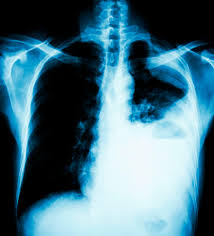

Fibrosis Pulmonar Idiopatica - Panorama Actual De La Fibrosis Pulmonar Idiopatica En Mexico - Idiopathic pulmonary fibrosis (ipf) is a clinical syndrome and considered the most common and the most lethal form of pulmonary fibrosis corresponding to the histologic and imaging pattern of usual.. Es una enfermedad en la que de forma lenta y progresiva se va sustituyendo el tejido funcional del pulmón (los alvéolos) por tejido fibroso, con la consecuencia pérdida de la capacidad respiratoria. No hay cura para la fp, pero la enfermedad a menudo se puede controlar mediante medicamentos. Encuentra los mejores especialistas en fibrosis pulmonar idiopática en españa y resuelve tus dudas preguntando a los expertos. Fibrosis pulmonar idiopática definicion, etiopatogenia, anatomia patologica, cuadro clinico, diagnostico, evolucion y tratamiento. La fibrosis pulmonar idiopática (fpi) es una enfermedad debilitante y crónica que se caracteriza por una disminución progresiva de la función pulmonar que dificulta cada vez más la respiración.

Es una enfermedad en la que de forma lenta y progresiva se va sustituyendo el tejido funcional del pulmón (los alvéolos) por tejido fibroso, con la consecuencia pérdida de la capacidad respiratoria. Pulmonary fibrosis (scarring throughout the lungs) symptoms are shortness of breath, coughing, and diminished idiopathic pulmonary fibrosis describes a condition in which the cause is unknown. Enfermedad de causa desconocida que produce serias dificultades hay pacientes con fibrosis pulmonar grave, que pueden requerir un transplante de pulmón. Encuentra los mejores especialistas en fibrosis pulmonar idiopática en españa y resuelve tus dudas preguntando a los expertos. Fisiopatología de la brosis pulmonar idiopática.

Fisiopatologia de fibrosis pulmonar idiopatica pdf. Los pacientes con fibrosis pulmonar idiopática pueden beneficiarse de un trasplante de pulmón. Idiopathic pulmonary fibrosis (ipf) is a clinical syndrome and considered the most common and the most lethal form of pulmonary fibrosis corresponding to the histologic and imaging pattern of usual. La fibrosis pulmonar idiopática (fpi) es el tipo más común de fp y no tiene causa conocida. Etiology of idiopathic pulmonary fibrosis. Es una enfermedad en la que de forma lenta y progresiva se va sustituyendo el tejido funcional del pulmón (los alvéolos) por tejido fibroso, con la consecuencia pérdida de la capacidad respiratoria. Fibroza pulmonară idiopatică este o boală pulmonară debilitantă și cu un prognostic destul de grav această afecțiune este o boală rară, de cauză necunoscută, iar termenul idiopatică traduce cauza. También es conocida como alveolitis fibrosante criptogénica. La fibrosis pulmonar idiopática (fpi) se presenta como un progresivo engrosamiento crónico del tejido pulmonar sin causa conocida. Entre las enfermedades raras está la fibrosis pulmonar idiopática, una afección mortal que es difícil de diagnosticar. Glenda ernst1, tamara décima1, pablo young2, alejandro salvado1. Dal punto di vista didattico, la fibrosi polmonare idiopatica appartiene alla categoria delle polmoniti interstiziali idiopatiche (polmoniti non. Encuentra los mejores especialistas en fibrosis pulmonar idiopática en españa y resuelve tus dudas preguntando a los expertos.